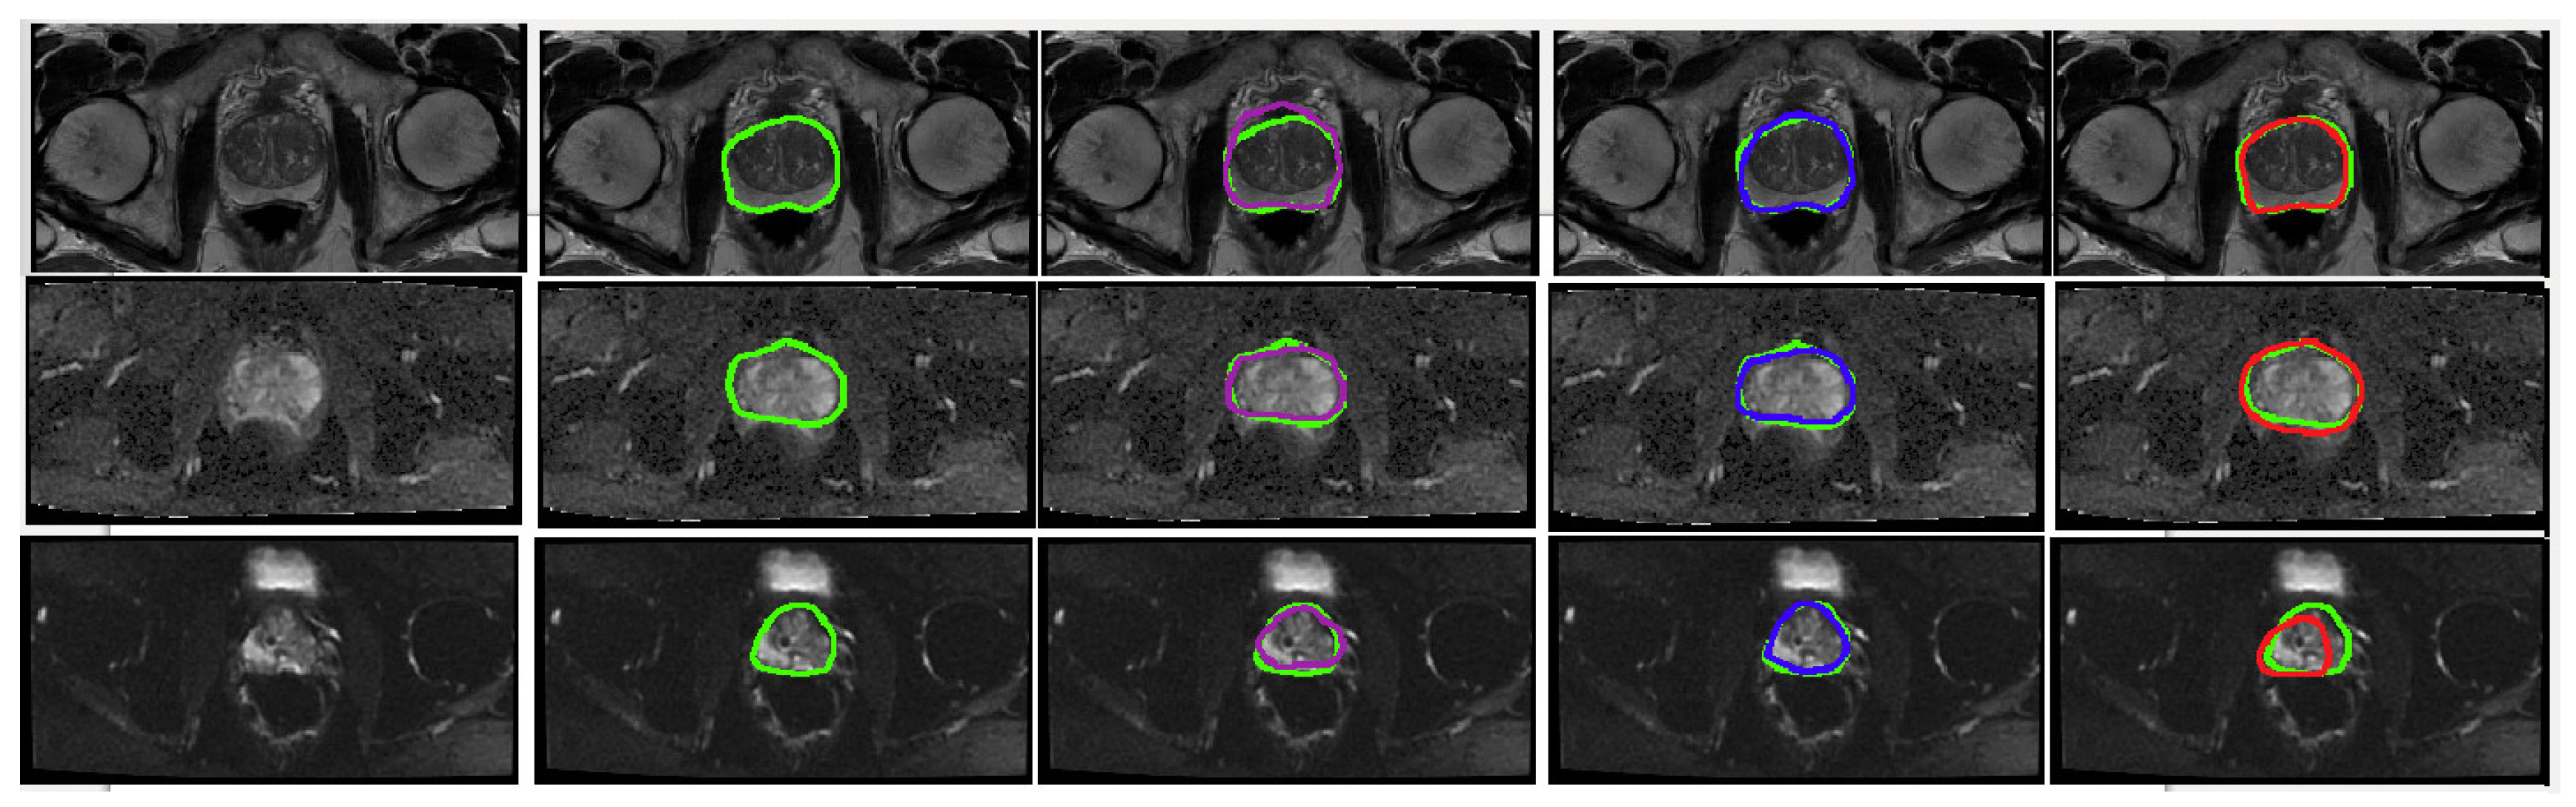

Figure 5.

Visual representation of the predicted segmentation for each model and each modality for a single slice from a case study. From the top row to the bottom: T2W, ADC and DWI. From left to right: Raw test image, Ground truth boundaries in green, U-Net’s prediction in purple, cGAN’s prediction in blue and cycleGAN prediction in red. The quantitative results show the best performance for cGAN followed by U-Net for all evaluation metrics. Scaled images are shown in Figure A1 for better visualisation.

Figure A1.

Visual representation of the predicted segmentation for each model and each modality for a single slice from a case study, where the prostate region is zoomed in and the image brightness is increased. From the top row to the bottom: T2W, ADC and DWI. From left to right: Raw test image, Ground truth boundaries in green, U-Net’s prediction in purple, cGAN’s prediction in blue and cycleGAN prediction in red. The quantitative results show the best performance for cGAN followed by U-Net for all evaluation metrics.